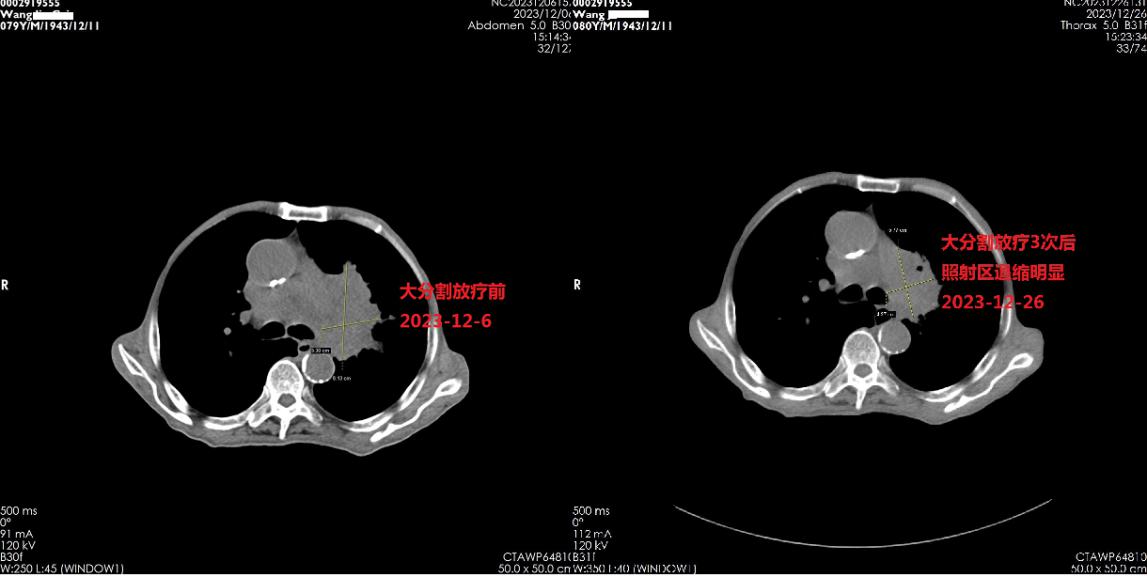

另一位80岁的王老先生是左肺广泛期小细胞肺癌患者,伴有慢阻肺、高血压病、糖尿病等基础疾病,2023年5月在确诊小细胞肺癌半年后,进行化疗联合免疫治疗、抗血管联合免疫治疗,但病情却进一步发展,2023年12月患者出现呼吸困难,遂来我院肿瘤内科二病区住院。蒋宗惠主任医师、董祥宁副主任医师与患者和家属充分沟通后,采取了基于T细胞调控免疫检查点抑制剂联合大分割放射治疗,在治疗3周后,患者身体内的肿块明显缩小,胸闷气喘症状明显缓解。